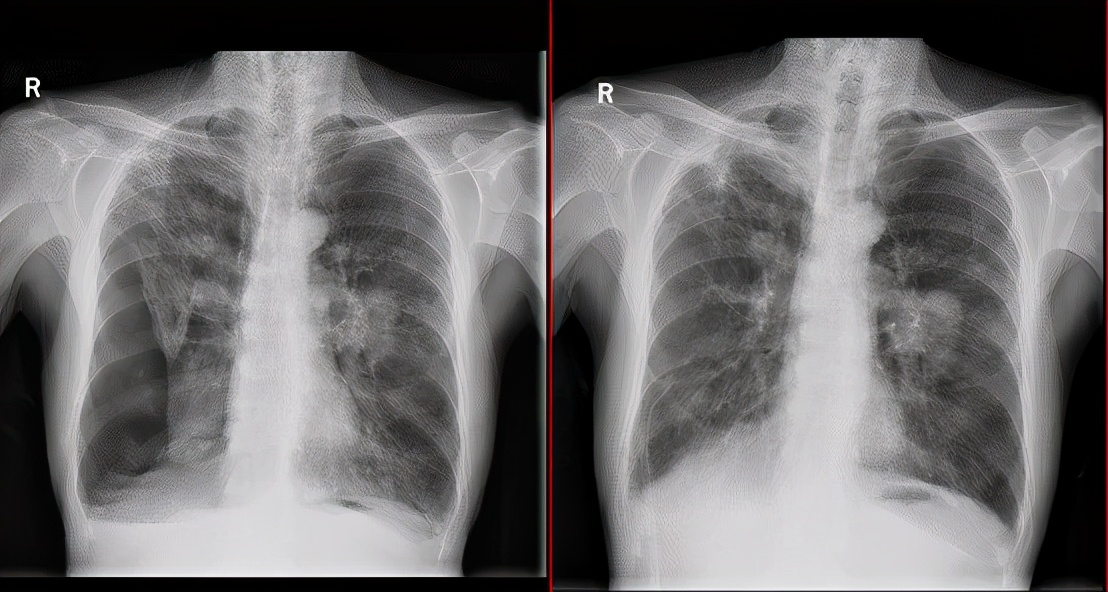

家属为病人办好住院手续后,祈福医院呼吸科主任接待了郭老先生,并且立即开始了会诊,通过胸部的CT造影后,大家发现郭老爷子的肺部真的已经到了病入膏肓的境地。

郭老爷子的双肺出现了严重肺气肿、肺大疱并发其他症状,而且郭老爷子的胸部引流管已经存在了三个月了,如此下去不但没有办法治好郭老先生的肺病,还会让他的生活质量严重下降。